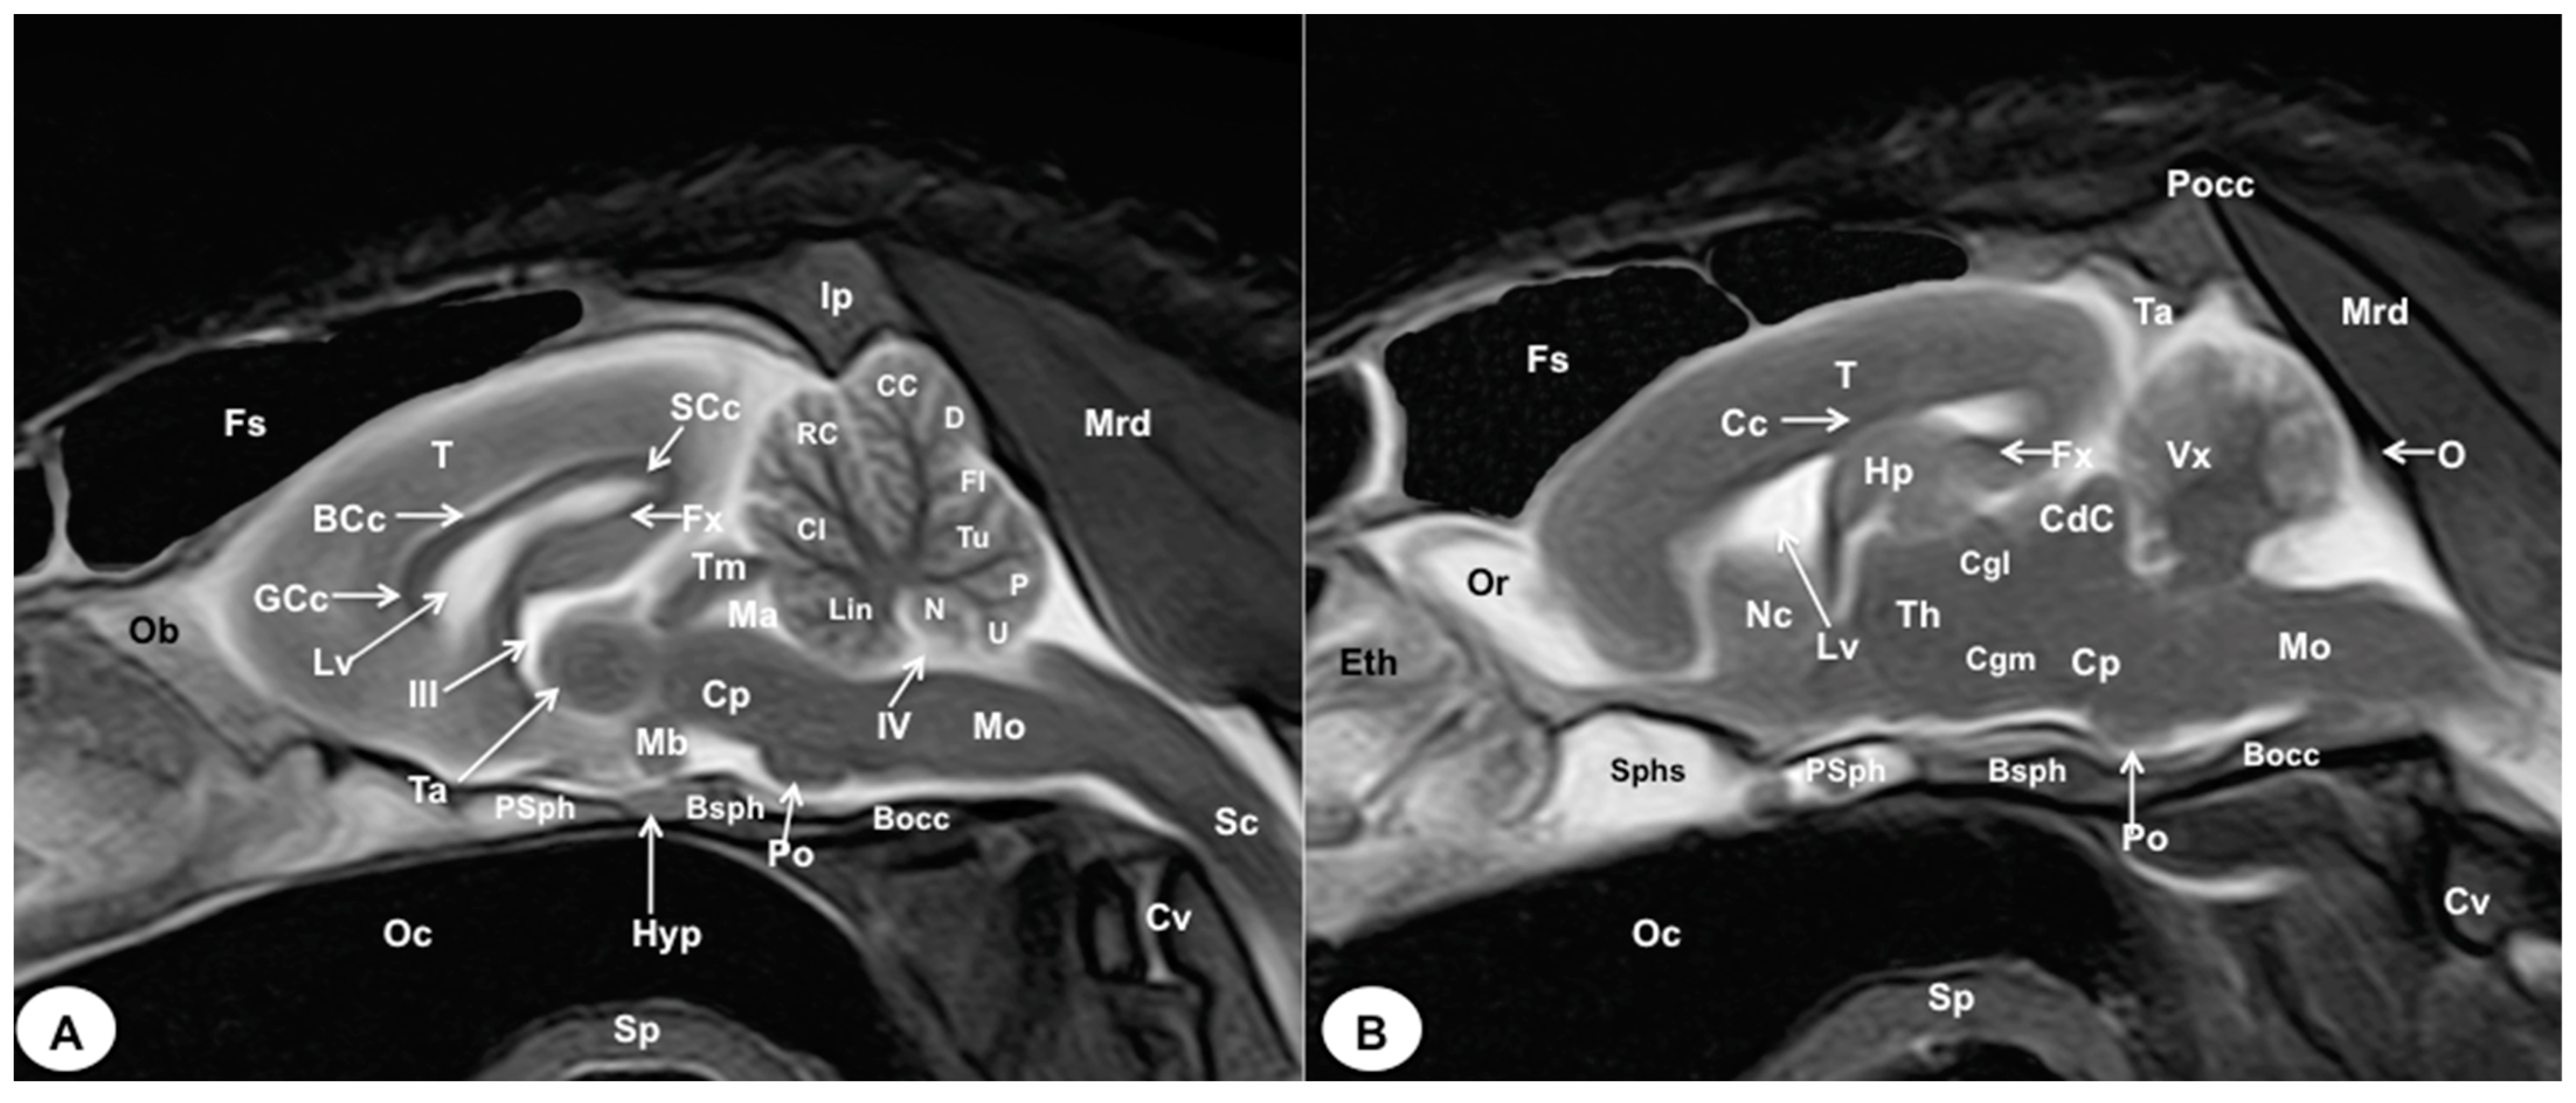

3.1. Anatomical Cross-Sections

3.2. Magnetic Resonance Imaging (MRI)